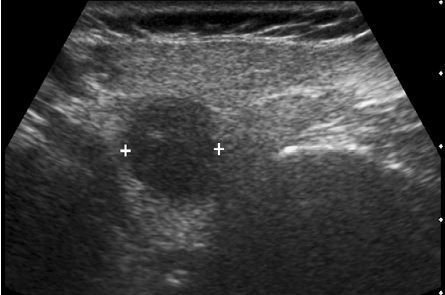

The gray-scale view shows a complex fluid

collection arising from the right kidney. In addition,

there is a simple-appearing, round, cystic structure

within the otherwise complex collection. The

power Doppler view shows flow in the apparent

cyst. All of these findings are consistent with a

pseudoaneurysm and adjacent hematoma.

Always put color Doppler on a “simple-appearing” cyst to make suer it is not something else!!!